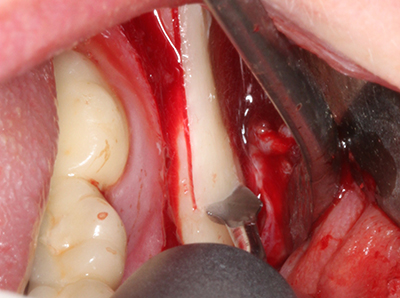

Autologous bone transplants are used in the form of blocks, shells, rings and are also combined with bone replacement materials as chips. If the implant site is prepared at the same time as the augmentation, various bone filter systems have proven effective for collecting the resulting bone chips. As an alternative, the implant site can be prepared using a low-speed device without irrigation. If an implant is not inserted, bone chips can be harvested from the periphery with bone scrapers. This is also possible with piezosurgery using specialized attachments that yield higher-quality bone chips compared chips harvested with round drills, as has been confirmed in a study comparing the two methods (Chiriac, Herten et al. 2005).

Piezosurgery has additional advantages when harvesting bone blocks. In addition to the high precision with osteotomy described above, the use of the thin saw tips specifically minimizes loss of material. Greater loss of material during harvesting can be expected with the thicker instrument tips, particularly when using Lindemann drills (Lakshmiganthan, Gokulanathan et al. 2012). The basal separation, which is necessary particularly for retromolar block transplants, is simplified by specially designed rectangular saws, with the result that piezosurgery is viewed as a precise, simple and safe procedure for harvesting retromolar bone blocks (Happe 2007) (Fig. 1-12).